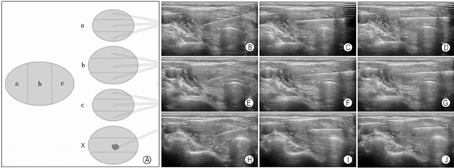

实践中,对于较大结节我们提倡采用基于"一针技术"的"9+X针道"穿刺模式,以最大化、全面化获取目标结节的穿刺标本。所谓"一针技术"是指穿刺针进入结节后,针尖仅在结节内作多次往复提插运动,穿刺针保持位于甲状腺内,不退出到腺体包膜外。在此基础上完成"9+X针道"穿刺取材。

"9+X针道"穿刺模式是指在甲状腺纵切面声像图上,将目标结节分为上、中、下三个分区,然后在横切面上对每个分区再分为前、中、后三个小分区,使用同一根穿刺针对9个小分区相继、连续穿刺取材,故整个病灶一次进针,便可从9个针道上吸取标本。"X"指不确定针数,若目标病灶内有微小钙化、血流信号异常丰富或无信号、弹性超声应变比值较大等特殊声像表现区域,则对其额外增加穿刺取材(targeted biopsy),吸取物涂布于另一张载玻片上,此即"9+X针道"穿刺模式的概念(图18)。

"9+X针道"穿刺模式在取材部位的全面性和均衡性、取材数量的充足性、取材质量的优化性、特征声像图表现对应性方面均体现出FNA当前的规范性和严谨性。